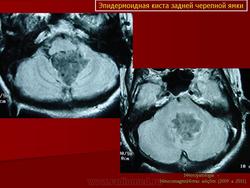

В большинстве случаев эпидермоидные кисты располагаются в ликвороносных путях головного мозга: в субарахноидальных цистернах или желудочковой системе. Распространение эпидермоидной кисты в пределах одной базальной цистерны встречается редко. Обычно, прорастая арахноидальные мембраны и трабекулы, переходят в соседние цистерны и занимают пространство, включающее несколько цистерн. Кроме этого, они способны прорастать твёрдую мозговую оболочку, разрушать костные структуры и расти экстракраниально.

Боковая цистерна моста довольно часто является местом первичной локализации эпидермоидной кисты. Дальнейший рост ее идет в направлении ската, супратенториально или в сторону краниоспинального перехода. При росте в направлении тенториального отверстия эпидермоидная киста распространяется в межножковую или охватывающую цистерны. При росте в сторону краниоспинального перехода, эпидермоидная киста через отверстия Люшка прорастает в полость четвёртого желудочка. Первичная эпидермоидная киста четвёртого желудочка аналогично может распространяться в мостомозжечковую цистерну.